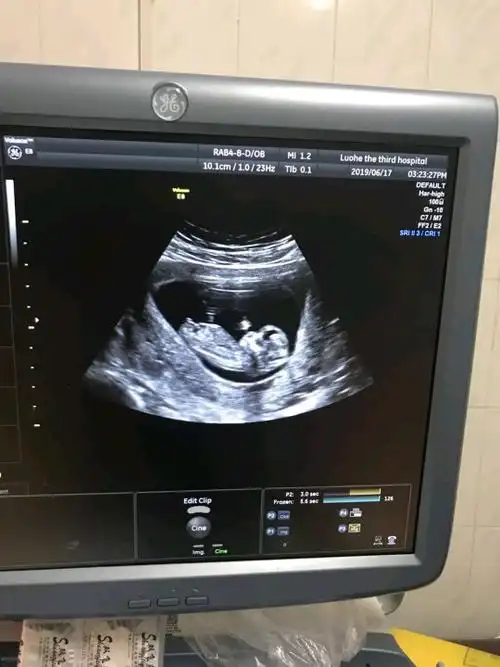

nt通过啦!有伙伴会看男女嘛

nt图上有三条线是不是生女孩的几率更大

nt 顺利通过,不知道是男宝还是女宝